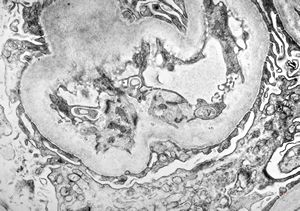

F,69y. | urinary bladder - malakoplakia